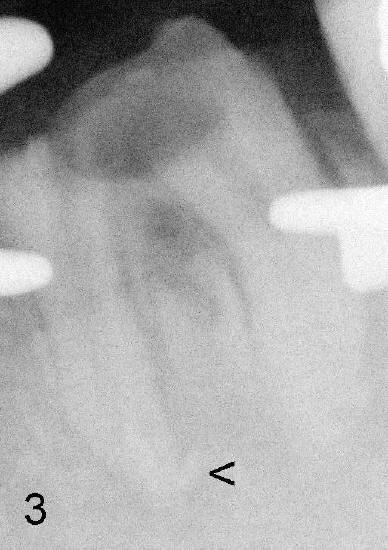

Fig.3 It appears that extruded mesial GP remains outside the apex (<) after master cones being removed, back to original article